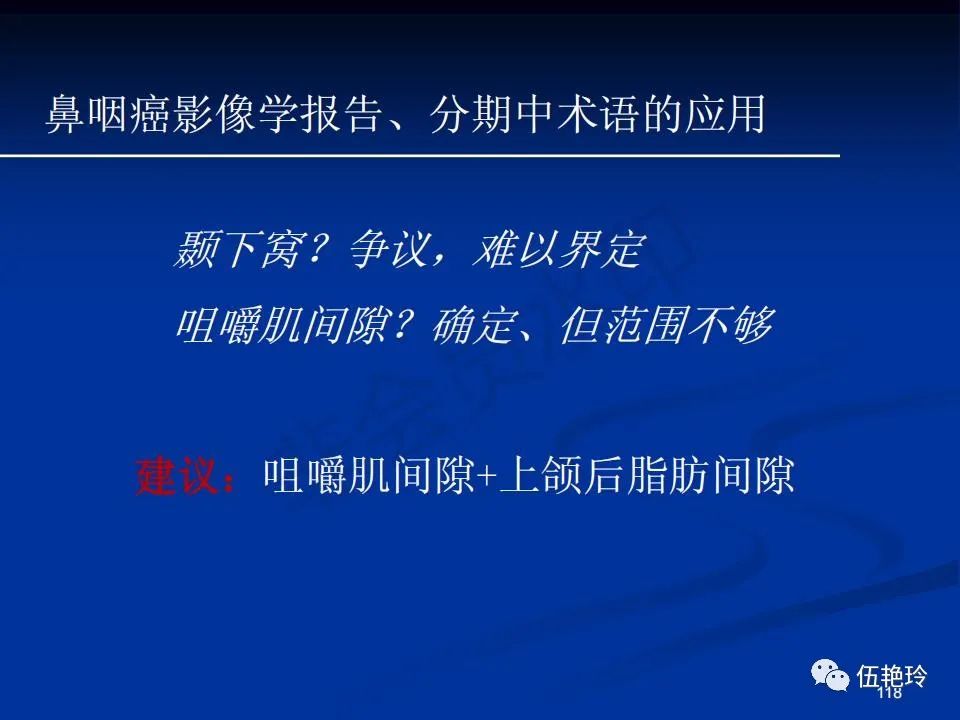

颞下窝与咀嚼肌间隙